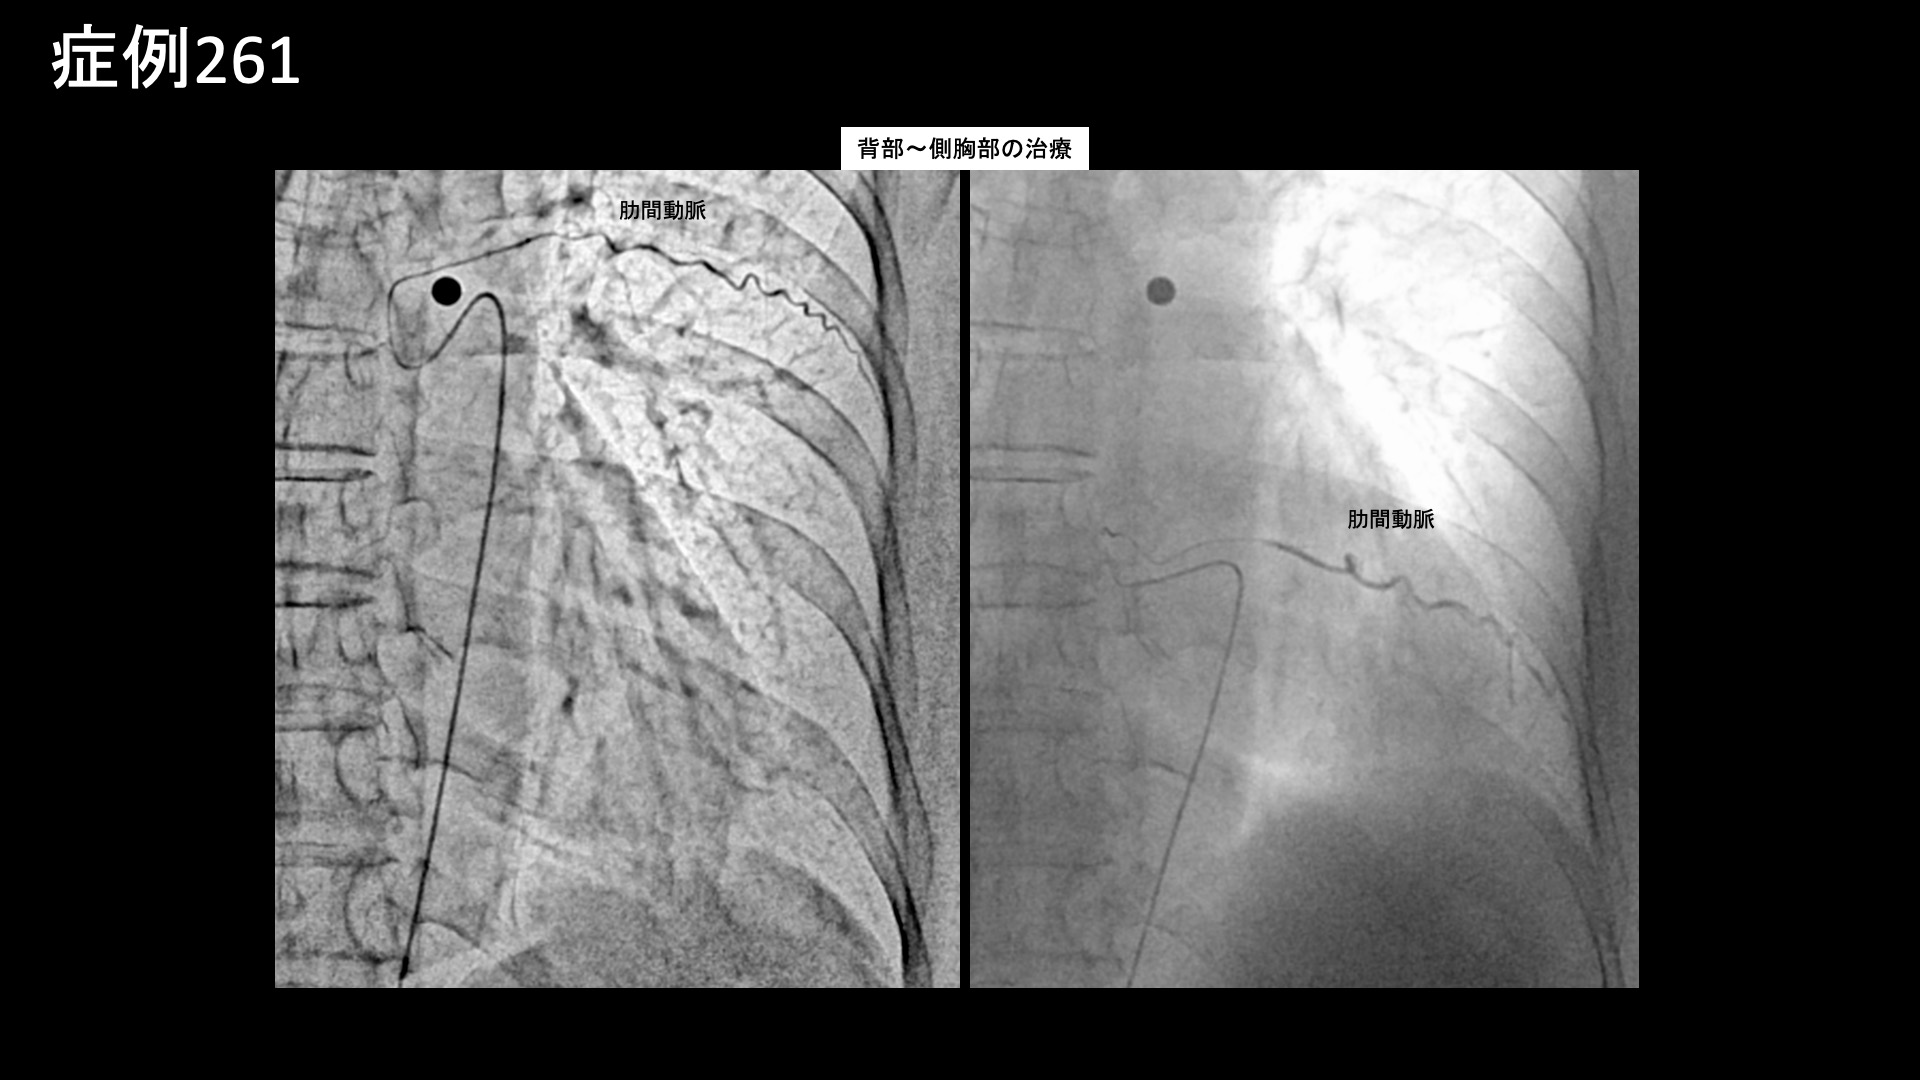

帯状疱疹後神経痛はモヤモヤ血管が描出されやすい疾患ではありませんので、通常、モヤモヤ血管を描出するためのDSA撮像という特殊な撮影条件で撮影することはありません。解剖学的な知識、および再現痛をたよりに治療を進めていきます。写真では、前胸部の主要責任血管である内胸動脈、脇から背中にかけて重要になってくる胸背動脈、および肋間動脈の血管造影画像を示しています。それぞれ再現痛が認められました。治療のやり残しがないよう、必要十分な範囲を治療して終了しました。

*再現痛とは、薬液投与時に普段の痛みが一定程度再現される現象です。責任血管の同定のための参考とします。